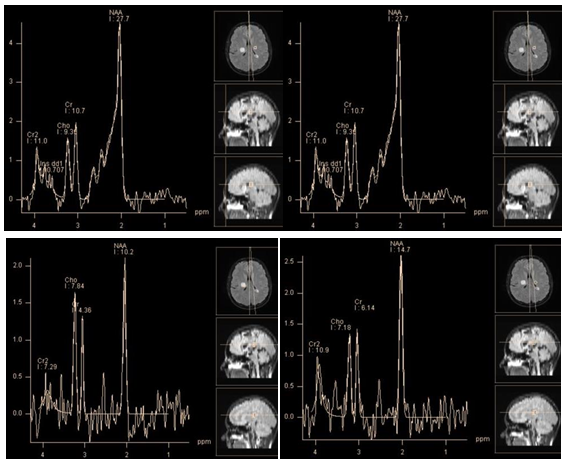

New studies that focus on glutamine/glutamate (2.05 - 2.6 ppm), and glutathione (2.95 ppm) peaks, convincingly demonstrate a high concentration of these metabolites (associated with metabolic cycle of alanine) in meningiomas22,25 (Figure 8). In our studies, all 25 (100%) meningiomas demonstrated a dominant concentration of the glutamine/glutamate complex. Kousi et al.,26 found a typical chemical compounds for meningiomas that can be detected at 3.8 ppm using short TE, as a "distinct peak" (Figure 8). In vitro studies suggest that the "distinct peak" is likely to consist of the sum of resonant frequencies of phosphoethanolamine, alanine, glutamine and glutamate.23 (In our study, in 24 of 25 of meningiomas a "distinct peak" was clearly present).

Figure 8 A typical metabolite profile of meningioma. PRESS TE 30 ms (a), PRESS TE 135 ms (b). Alanine peak (1.5 ppm) partially merge with those of lactate (a,b). The dominant peaks of Glx (a). High choline peak. "The distinct peak" * (a) also can be seen on the spectra, obtained with TE 135 ms at 3.8 ppm (b).

Figure 9 Spectra of pituitary adenoma. PRESS TE 30 ms (a), PRESS TE 135 ms (b) in comparison with suprasellar meningioma. PRESS TE 30 ms (c), PRESS TE 135 ms (d). Peak at 2.0 ppm in the spectra of adenoma, corresponding to NAA resonant frequency, is evident on both short (a) and Intermediate (b) TE. High peak myo-inositol at 3.58 ppm is present (a) there are no peaks of alanine and lactate, and low concentrations of glutamine/glutamate complex (a).